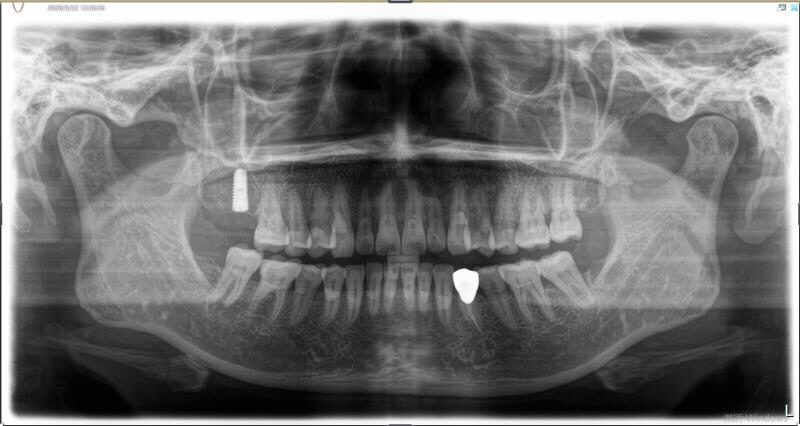

今天给大家分享的病例是一位中年女性,17缺失,由于长时间未修复,47伸长,留给17修复的空间不足。

老卢给她的治疗方案是:17种植修复,47根管治疗后截冠、高嵌体修复。这样可以最大限度的增加患者的咀嚼效率。